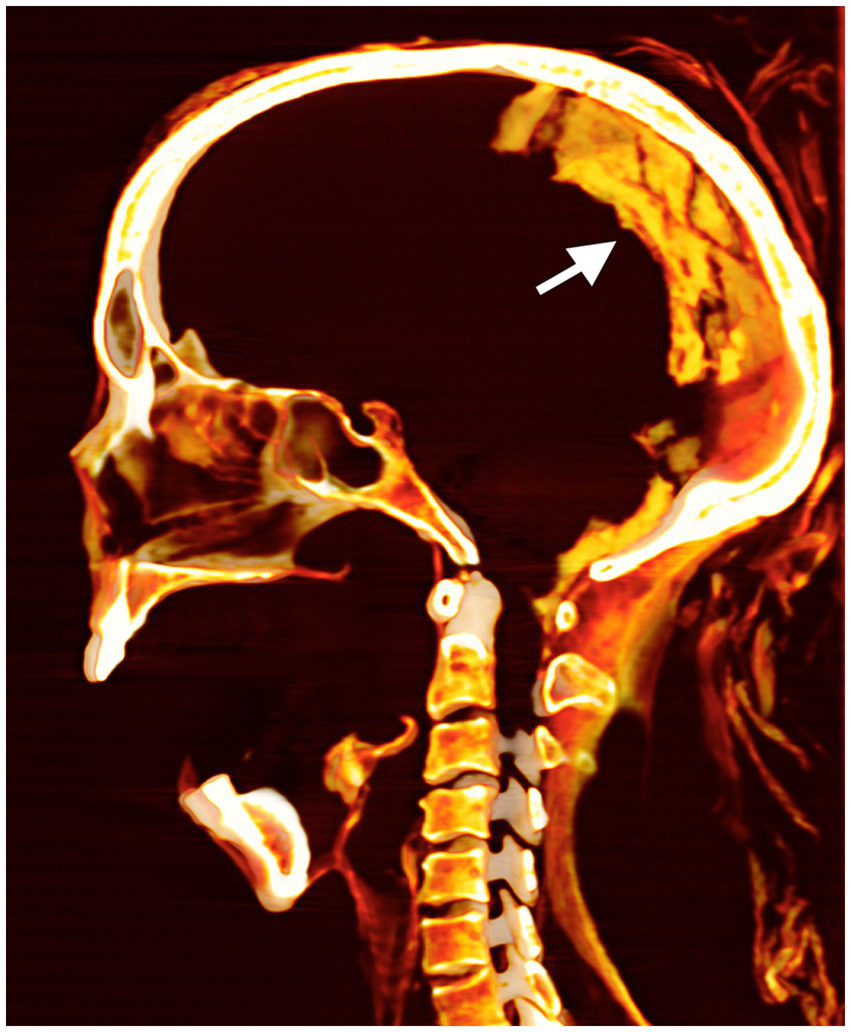

Intact skull is noted with no evidence of brain removal (excerebration) attempt. The desiccated brain occupies the posterior part of the skull cavity (Figure 6). There is no evidence of any foreign materials or packing in the orbits, nostrils, or ear openings.

Figure 6

The mid-sagittal three-dimensional CT image of the head of anonymous mummified woman (referred to as CIT8). It shows an unbroken cribriform plate, with the preserved desiccated brain resting at the back of the skull (arrow). The mummy with a widely open mouth was found at Luxor, Egypt, near Senmut’s service tomb, the architect during Queen Hatschepsut’s reign (1479–1458 BC).

The embalmers did not excerebrate the mummy since CT scans showed the skull base’s integrity and the presence of a dry shrunken brain at the back of the cranial cavity CIT8. Although excerebration is seen in those who benefited from the New Kingdom’s classic mummification, CT scanning revealed that brain removal was not performed on royals from the early 18th Dynasty (1550–1295 BC), including Amenhotep I (1525–1504 BC), Thutmose II (1492–1479 BC), and Thutmose III (1479–1425 BC) (37, 38).